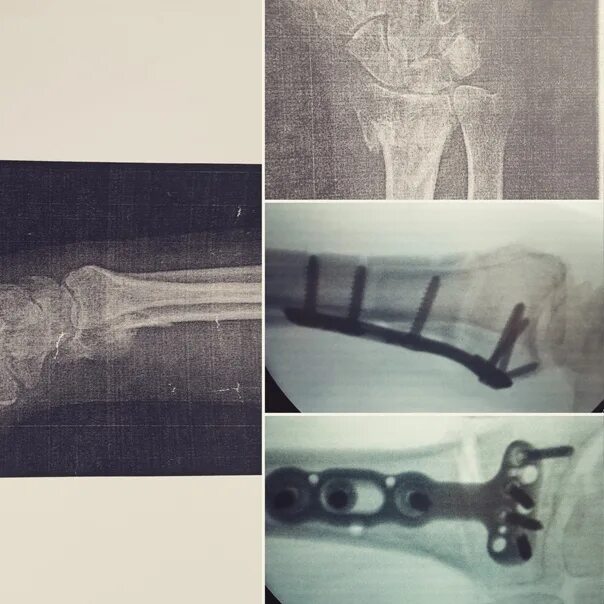

Перелом руки срок срастания